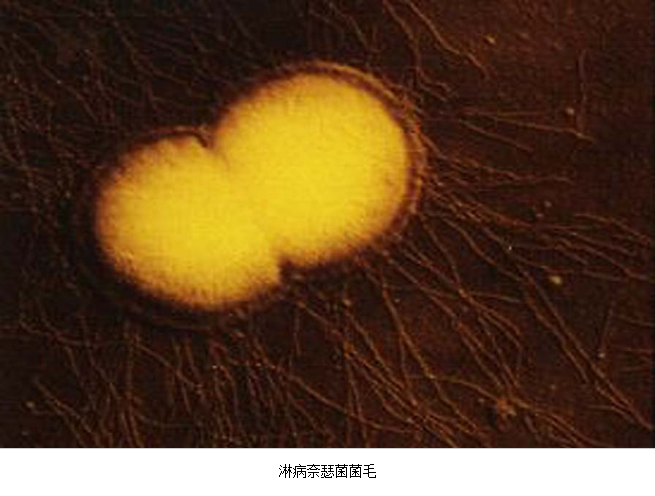

急性子宫颈炎的病原体:①性传播疾病病原体:淋病奈瑟菌及沙眼衣原体,主要见于性传播疾病的高危人群;②内源性病原体:部分子宫颈炎的病原体与细菌性阴道病病原体、生殖支原体感染有关。但也有部分患者的病原体不清楚。沙眼衣原体及淋病奈瑟菌均感染子宫颈管柱状上皮,沿黏膜面扩散引起浅层感染,病变以子宫颈管明显。除子宫颈管柱状上皮外,淋病奈瑟菌还常侵袭尿道移行上皮、尿道旁腺及前庭大腺。

3.病原体检测 应作衣原体及淋病奈瑟菌的检测,以及有无细菌性阴道病及滴虫阴道炎。检测淋病奈瑟菌常用的方法有:①分泌物涂片革兰染色,查找中性粒细胞内有无革兰阴性双球菌,由于子宫颈分泌物的敏感性、特异性差,不推荐用于女性淋病的诊断方法。②淋病奈瑟菌培养,为诊断淋病的金标准方法。③核酸检测,包括核酸杂交及核酸扩增,尤其核酸扩增方法诊断淋病奈瑟菌感染的敏感性及特异性高。检测沙眼衣原体常用的方法有:①衣原体培养,因其方法复杂,临床少用。②酶联免疫吸附试验检测沙眼衣原体抗原,为临床常用的方法。③核酸检测,包括核酸杂交及核酸扩增,尤以后者为检测衣原体感染敏感、特异的方法。但应做好质量控制,避免污染。